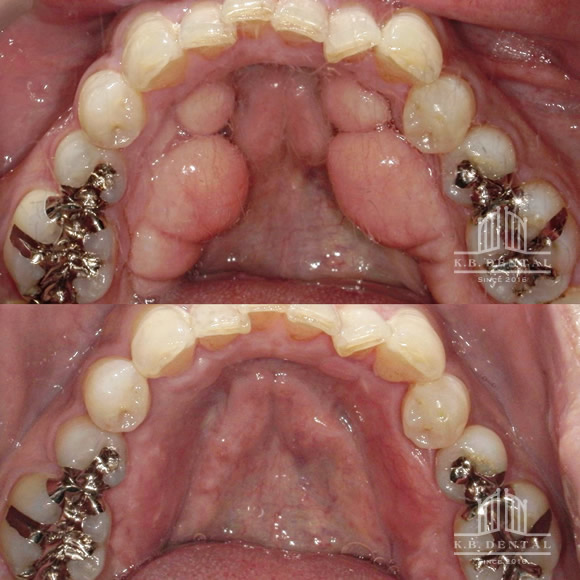

下顎骨隆起除去 症例2(下顎舌側両側骨隆起)

下顎の舌側に発生した骨隆起です。手術時間は約2時間で、静脈麻酔下で除去します。

下顎骨隆起除去 症例3(下顎舌側両側骨隆起)